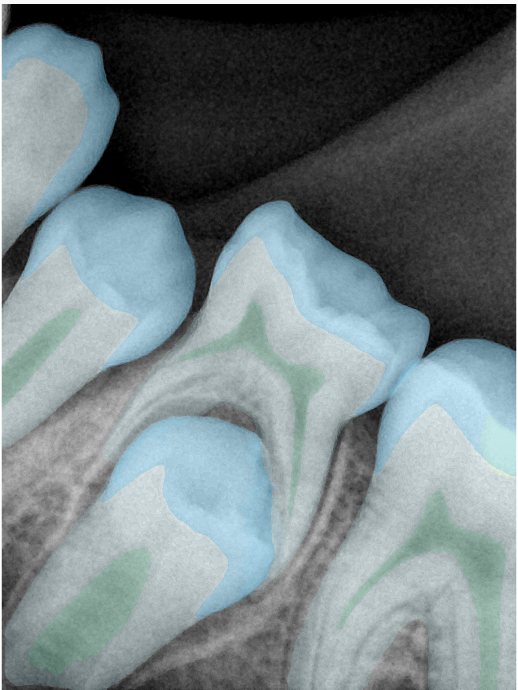

第二版算法问题测试

| 第一版 | 第二版 | 是否解决 | |

|---|---|---|---|

![]() | ![]() ![]() 边角识别有问题 龋齿识别不全 牙髓识别不全 | ![]() | 解决 |

![]() | ![]() 边角识别有问题 识别信息有误 自查(牙冠识别不全) | ![]() | 解决 |

![]() | ![]() ![]() 边角识别有误 大范围填充识别遗漏 | ![]() | 解决 |

![]() | ![]() 识别信息不全 | ![]() | 解决 |

![]() | ![]() ![]() 边角问题 牙胶识别不全 牙冠识别不全 | ![]() | 解决 |

![]() 换图片 | ![]() | ![]() 牙冠部分稍微白了一些就识别成小范围修补,部分判断异常 | 部分解决,修复类略敏感,牙冠部分稍微白了一些就识别成小范围修补,部分判断异常。 |

![]() | ![]() ![]() 牙冠识别不全 牙髓不全 根尖炎龋齿识别有误 | ![]() | 解决 |

![]() | ![]() | ![]() | 解决 |

![]() 换图片 | ![]() | ![]() | 解决 |

![]() | ![]() 牙冠识别有误 | ![]() | 解决 |

![]() 换图片 | ![]() ![]() 边角识别有误 | ![]() 修复类敏感 | 部分解决,图像过白,导致修复类判断异常。 |

![]() 换图片 | ![]() 牙冠识别不全 | ![]() 修复类敏感 | 部分解决,图像过白,导致修复类判断异常 |

结论:修复类出现了不鲁棒的情况,后续需要加入轮廓的扩充数据进行增强。